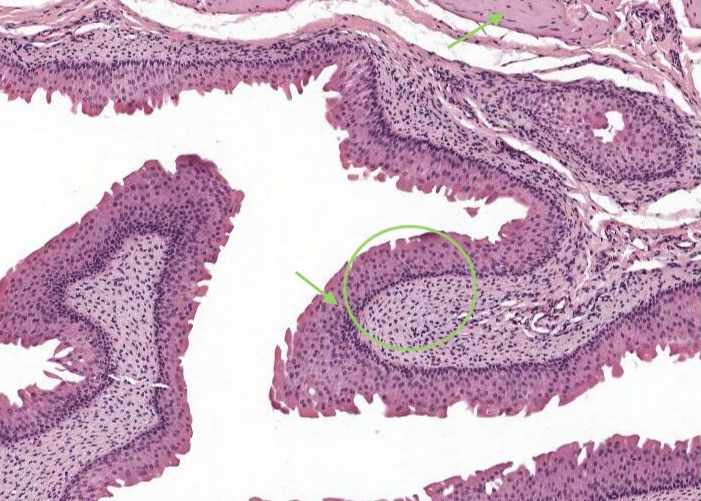

The ureter and also the other passages within the kidney through which urine flows i.e. the calyces and renal pelvis, are lined by transitional epithelium (often referred to as urothelium). The details of the layers of cells within this type of epithelium is best described in the later item "lumenal epithelium" of the bladder but generally it is 2-3 cell layers thick in the minor calyces but much thicker as you see here in the ureter and then the bladder.

Transitional epithelium is impermeable to water and salts and can accomodate the distension of the bladder as it fills with urine. In this image of "relaxed bladder" there are about 8 cell layers but make sure you notice how these layers "flatten out" in the "stretched bladder" image in the later item. Notice how the surface cells are cuboidal and bulge into the lumen of the bladder but their apex is curved or shaped like a dome so they are often referred to as "umbrella cells". The connective tissue below the epithelium is very cellular.

Even at the light microscope level, careful examination of the apical plasma membrane of an umbrella cell reveals a slightly thicker/denser area called plaques. In a relaxed bladder many plaques have invaginated into the cell and so the contour of the epithelial surface appears "scalloped".